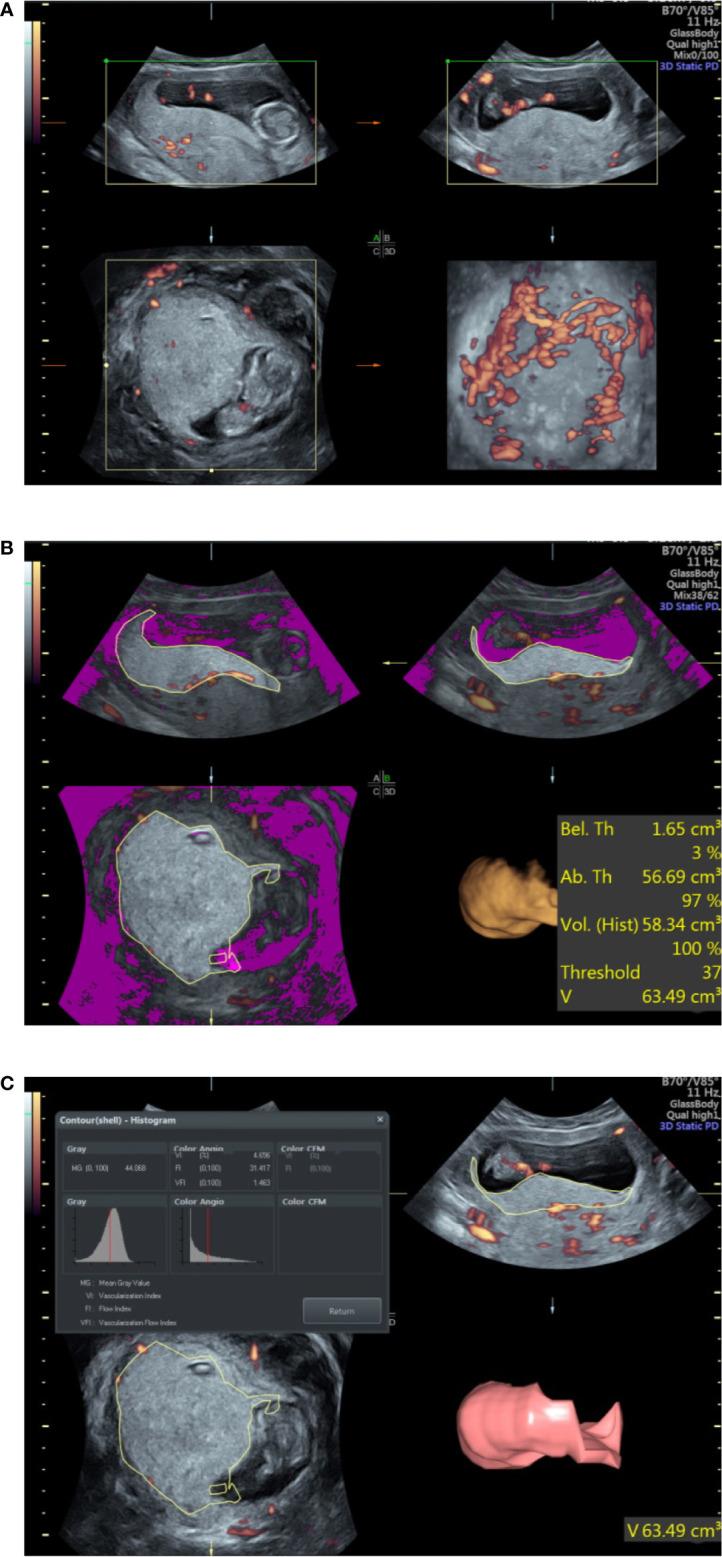

This was a prospective study of singleton pregnancies who took the early nuchal translucency examination from January 2018 to September 2019. Data on PV and vascular indices including vascularization index (VI), flow index (FI), and vascularization flow index (VFI) between pregnant women with and without GDM were measured by 3D Power Doppler ultrasound machine. Univariate and multivariate logistic regression determined the association between risk factors and GDM. Receiver operating characteristic (ROC) and area under the ROC curve (AUC) were applied to evaluate the diagnostic value of different parameters for GDM.

Of the 141 pregnant women enrolled, 35 developed GDM and 106 did not. The maternal age and gravida in the GDM group were significantly higher than that in the non-GDM group. The PV, VI, FI, and VFI in the GDM group were significantly lower than that in the non-GDM group. There were no significant differences in other clinical parameters between the two groups. After adjustments in multivariate logistic regression analysis, significant differences were observed in VI [odds ratio (OR) = 0.98, 95% confidence interval (CI) = 0.951-1.002], FI (OR = 0.93, 955 CI: 0.86-1.00), and VFI (OR = 0.67, 95% CI = 0.52-0.87). ROC analysis indicated that the combination of maternal age, gravida, PV, and VFI was more accurate as a marker for detecting GDM than the PV, VI, FI, or VFI alone.